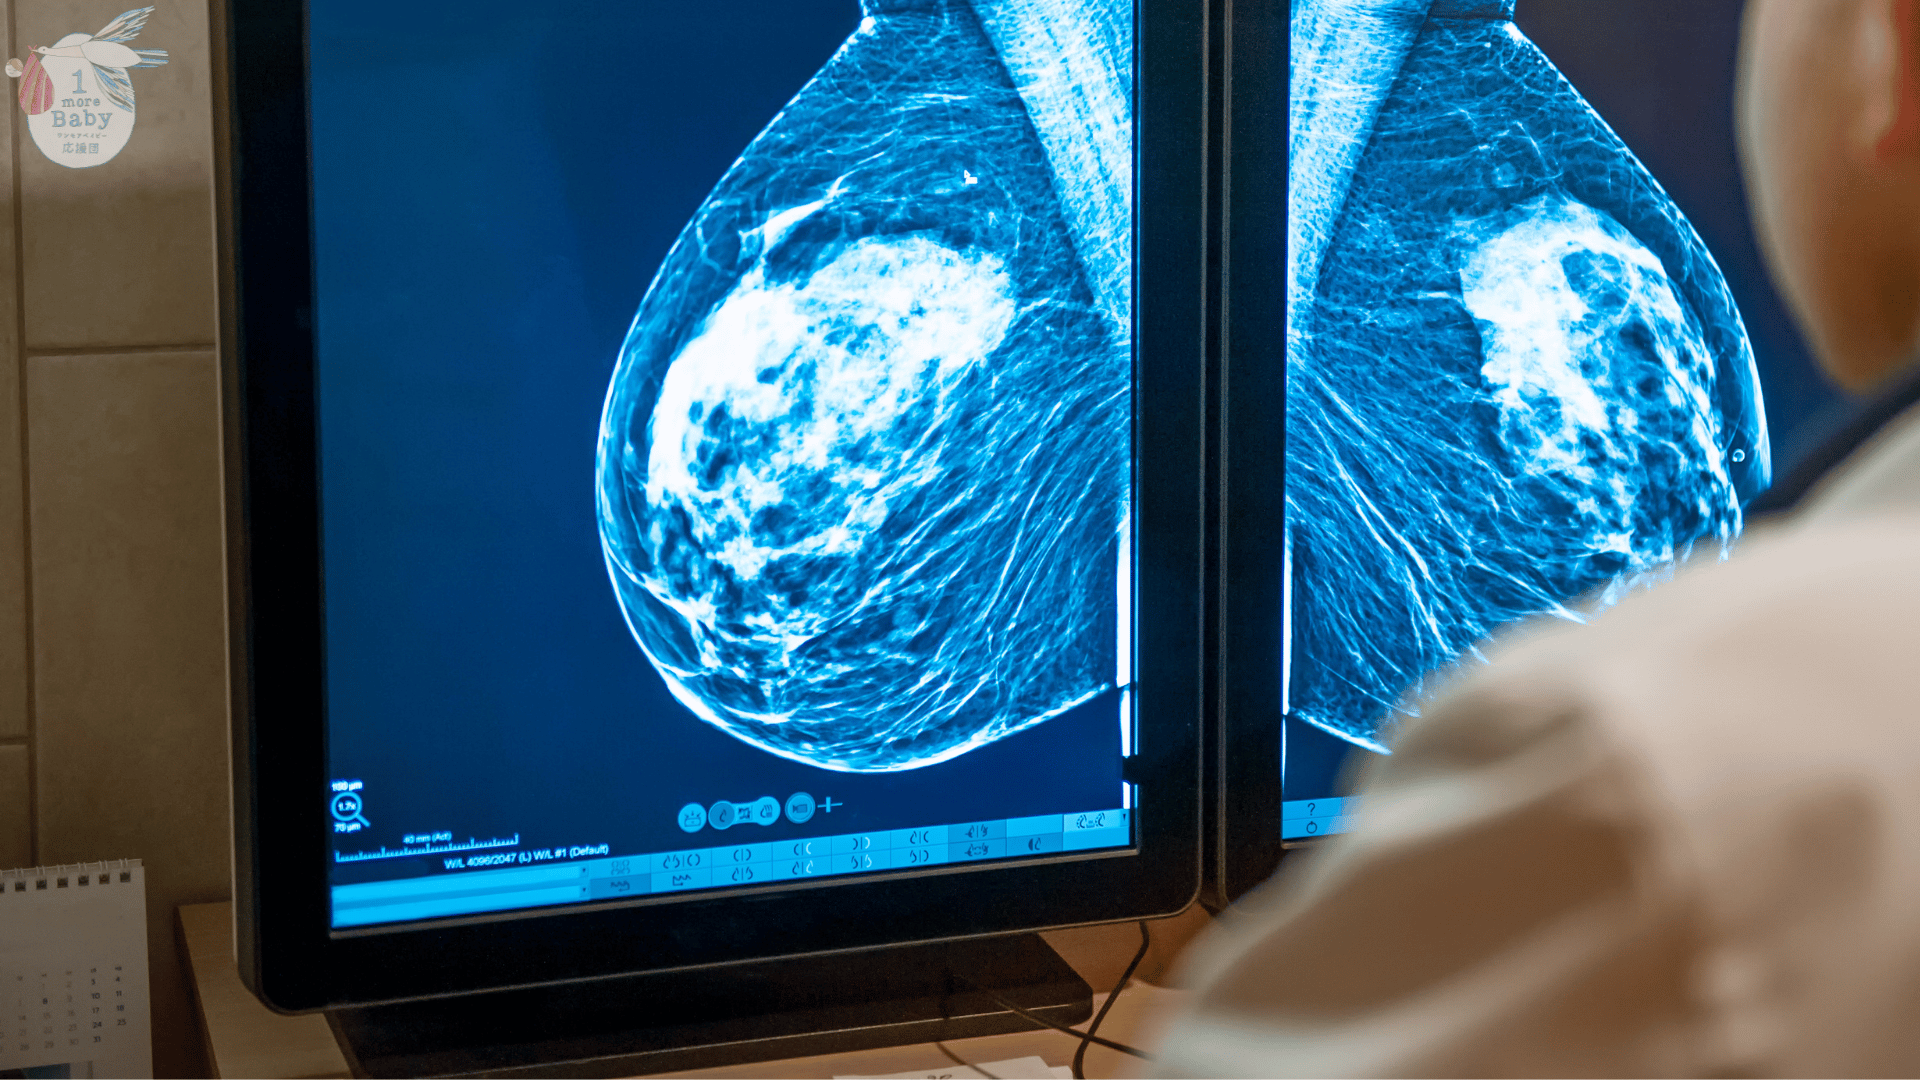

ピルを使用する前に知っておきたいこと〜成分によって異なる可能性がある乳がんリスク〜

現在、女性ホルモンは、多嚢胞性卵巣症候群などの卵巣機能不全に伴う月経不順、不正性器出血、月経前緊張症、更年期障害、子宮内膜症に伴う月経困難症などの疾患の場合や、健康状態における避妊目的など、いろいろな用途で用いられています。これらの治療効果や避妊効果はとても良く汎用性が高いのですが、一方でホルモン使用によるリスクも指摘されています。そのリスクの代表的な疾患は乳がんであり、近年、乳がんの発生率は閉経前の女性で増加しています。世界的な予測では、2040年までに年間300万人以上の新規発症者と100万人以上の死亡が推定されています。

ピルなどのホルモン避妊薬は、乳がんリスクの要因であることはすでに広く知られており、個人レベルでは小幅なリスク上昇をもたらします。しかし、ホルモン避妊薬が広範に使用された場合、国や世界の人口レベルでは大きな影響をもたらします。エストロゲンが乳腺上皮細胞増殖やがん遺伝子の増幅を介して乳がんを促進するという役割はよく知られていますが、プロゲステロンや合成プロゲスチンの役割についてはまだはっきりせず、一部の研究では乳腺細胞の増殖を刺激する可能性も示唆されていました。